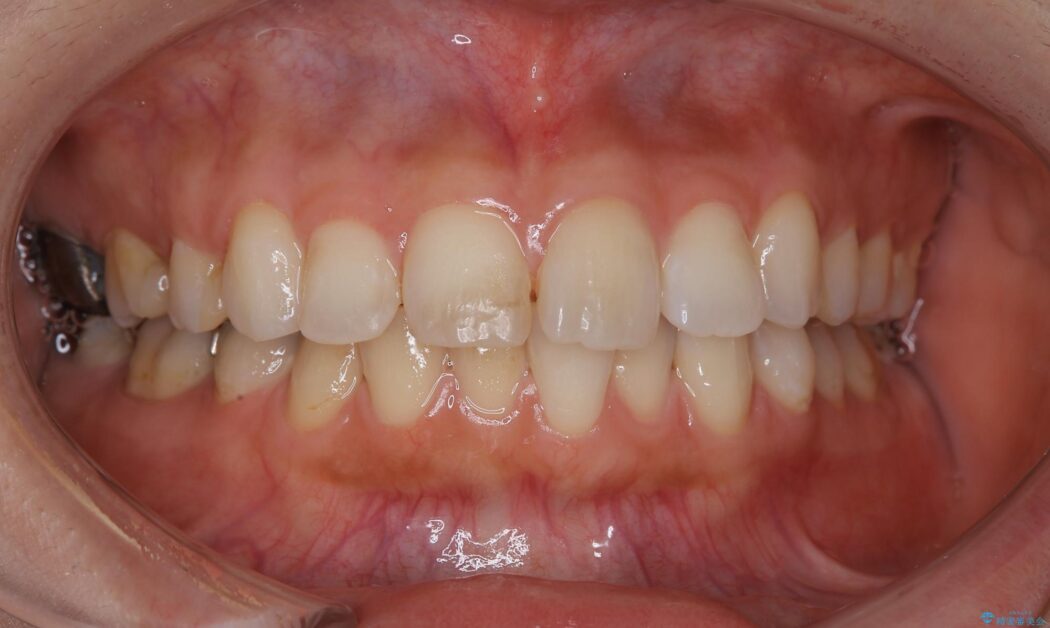

抜歯矯正後の後戻りについてご相談にいらした患者様です、

後戻りの程度としては軽度なので、治療期間としては短く終えることが出来ました。

前歯の正中線も改善され大変満足していただきました。